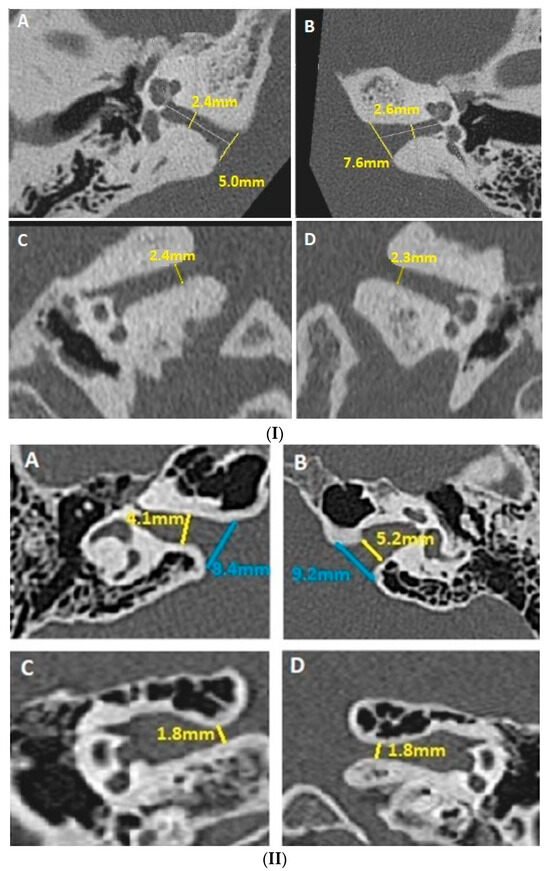

- Evaluation of the smallest anteroposterior and craniocaudal IAC diameters, both in the axial and coronal planes, after measuring the IAC length (Figure 1(I,II));

- Evaluation of anteroposterior and craniocaudal diameters of the IAC (Figure 2(I,II)).